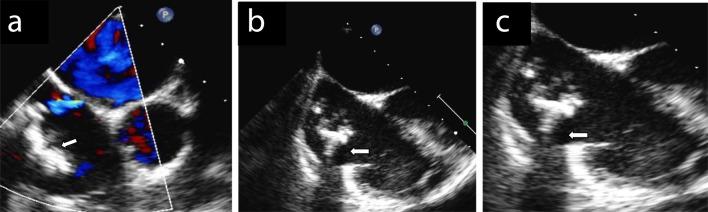

Catheter-related central thrombosis is a rare complication of long-term central line. We describe the case of an asymptomatic boy who was diagnosed a calcified thrombus in right atrium eight years after the removal of a long-term central venous device. Although the most appropriate therapeutic approach for managing floating right heart thrombi remains to be determined, surgical removal is an effective and safe procedure for calcified long-standing thrombus and it is to be preferred in elective conditions especially in young asymptomatic patients without hemodynamic involvement, that are at low risk of surgery-related morbidity and mortality.

导管相关的中心静脉血栓形成是长期中心静脉置管的一种罕见并发症。我们描述了一例无症状男孩的病例,该男孩在拔除长期中心静脉装置八年后被诊断出右心房有钙化血栓。尽管处理漂浮性右心血栓的最合适治疗方法仍有待确定,但手术切除对于钙化的长期血栓是一种有效且安全的方法,在择期情况下,尤其是对于没有血流动力学受累、手术相关发病率和死亡率风险较低的年轻无症状患者,手术切除是首选。